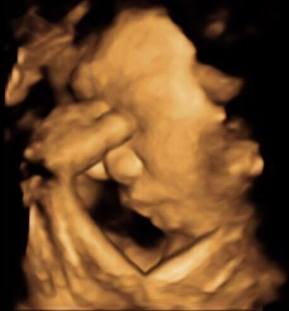

我們診斷了一個肢體缺陷的孩子

父母親是我們之前的醫療同業

專門從事復健專業

其實一開始

我心中想的是

這個孩子太幸福了

有最懂這方面的父母親來幫她做治療

但是很訝異的

後來這對父母親還是選擇了終止妊娠